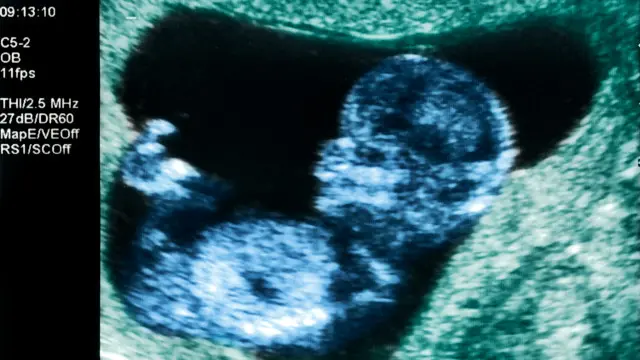

وقالت إن مثل أولئك السيدات ربما يحتجن إلى مزيد من الفحص، مثل المسح بالموجات فوق الصوتية، خلال فترة الحمل.